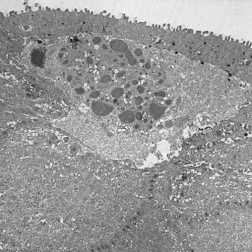

The primary pathology of MECD lies in the corneal epithelium and its basement membrane. Histopathologically, it is described by the development of clusters of small, clear intraepithelial cysts diffusely distributed at different levels within the corneal epithelium, which is irregular in thickness.[11] The transparent microcysts are roughly the same size and are mostly found in the basal epithelial cells. They contain degenerated epithelial cells and cellular debris that are periodic acid-Schiff (PAS) positive[4] and diastase- and neuraminidase- resistant.[11] Degenerated cellular debris within the intraepithelial microcysts manifests autofluorescence in ultraviolet (UV) light and it stains with the Hale colloidal iron technique for negatively charged substances such as glycosaminoglycans (GAGs). Other distinct pathological findings include the presence of electron-dense filamentary and granular material, the pathognomonic so-called peculiar substance, in the epithelial cells, and vacuolated, homogenous substance in the epithelial cysts (most commonly) and epithelial cells.[4] They may coalesce to form refractile lines and become more opaque.[17] The epithelium adjacent to the cysts remains clear.[5] Light microscopy shows the epithelial basement membrane to appear coarse, variably abnormally thickened, and multilaminar. Bowman layer and the corneal stroma are spared and remain intact.